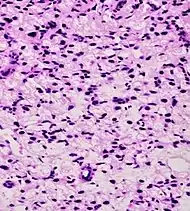

| Acinar adenocarcinoma - 93%[2] | Adenocarcinoma (not otherwise specified/ conventional/ usual acinar)[3] |

77%[notes 2] | 54%[notes 2] | ![]() |